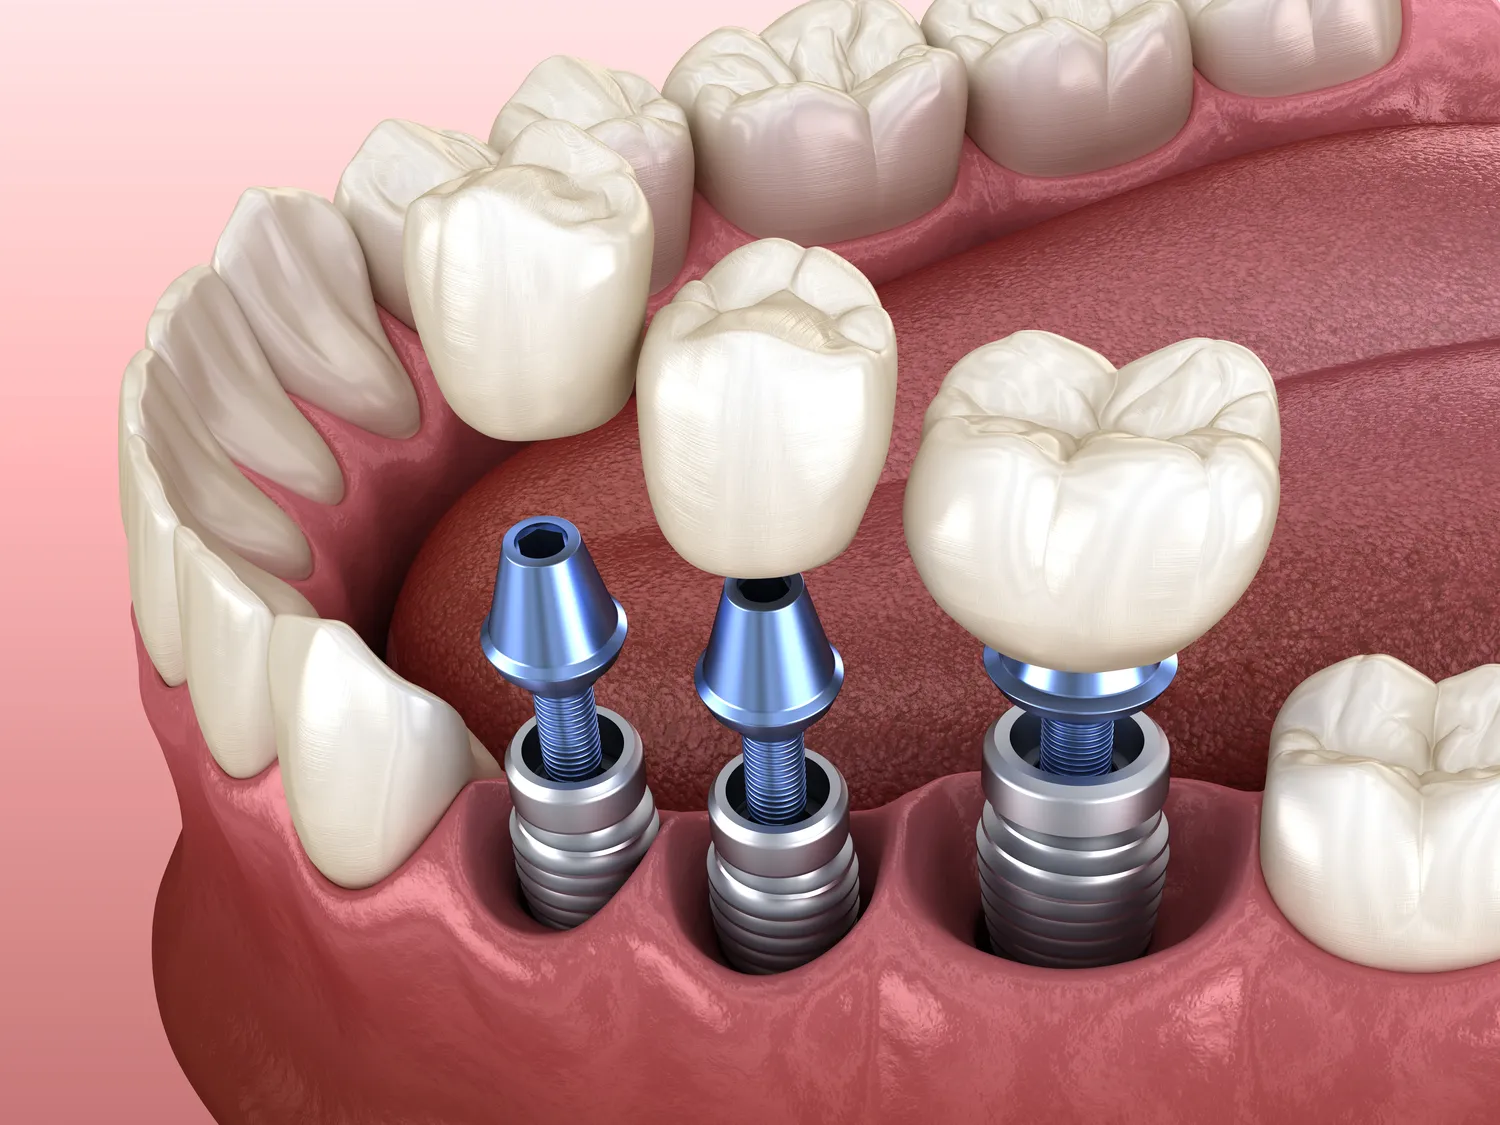

Rodzaje implantów różnią się w zależności od ich przeznaczenia oraz materiałów, z których zostały wykonane. W stomatologii najczęściej stosowane są implanty tytanowe, które charakteryzują się wysoką biokompatybilnością oraz odpornością na korozję. Tytan jest materiałem, który dobrze integruje się z kością, co sprawia, że implanty te są trwałe i stabilne. W ortopedii oprócz tytanu stosuje się również implanty wykonane z innych stopów metali oraz materiałów kompozytowych, które mogą być lżejsze lub bardziej elastyczne. W chirurgii plastycznej natomiast popularne są implanty silikonowe, które zapewniają naturalny wygląd i uczucie dotyku. Każdy rodzaj implantu ma swoje zalety i wady, dlatego ważne jest, aby lekarz dostosował wybór do indywidualnych potrzeb pacjenta oraz jego stanu zdrowia.

Proces wszczepiania implantów zazwyczaj rozpoczyna się od dokładnej diagnostyki oraz planowania zabiegu. Lekarz przeprowadza badania obrazowe, takie jak rentgen czy tomografia komputerowa, aby ocenić stan kości oraz określić najlepszą lokalizację dla implantu. Następnie pacjent otrzymuje znieczulenie miejscowe lub ogólne w zależności od zakresu zabiegu. Samo wszczepienie implantu polega na precyzyjnym umiejscowieniu go w kości lub tkankach miękkich. Po zakończeniu zabiegu pacjent musi przestrzegać zaleceń lekarza dotyczących pielęgnacji miejsca operacyjnego oraz unikania nadmiernego obciążenia przez określony czas. Proces gojenia może trwać od kilku tygodni do kilku miesięcy, a jego długość zależy od rodzaju implantu oraz indywidualnych predyspozycji organizmu pacjenta.

W ostatnich latach technologia związana z implantami rozwija się w szybkim tempie, co pozwala na wprowadzenie innowacyjnych rozwiązań poprawiających skuteczność oraz komfort pacjentów. Jednym z najnowszych trendów jest stosowanie implantów wykonanych z materiałów biokompozytowych, które łączą zalety tytanu i innych substancji organicznych, co sprzyja lepszej integracji z tkankami ciała. Ponadto rozwój technologii druku 3D umożliwia tworzenie spersonalizowanych implantów dostosowanych do indywidualnych potrzeb pacjenta, co zwiększa szanse na sukces zabiegu. W stomatologii coraz częściej stosuje się także techniki cyfrowe do planowania zabiegów oraz precyzyjnego umiejscawiania implantów, co minimalizuje ryzyko błędów chirurgicznych. W ortopedii nowoczesne implanty są projektowane tak, aby były lżejsze i bardziej wytrzymałe, co przekłada się na większy komfort użytkowania.